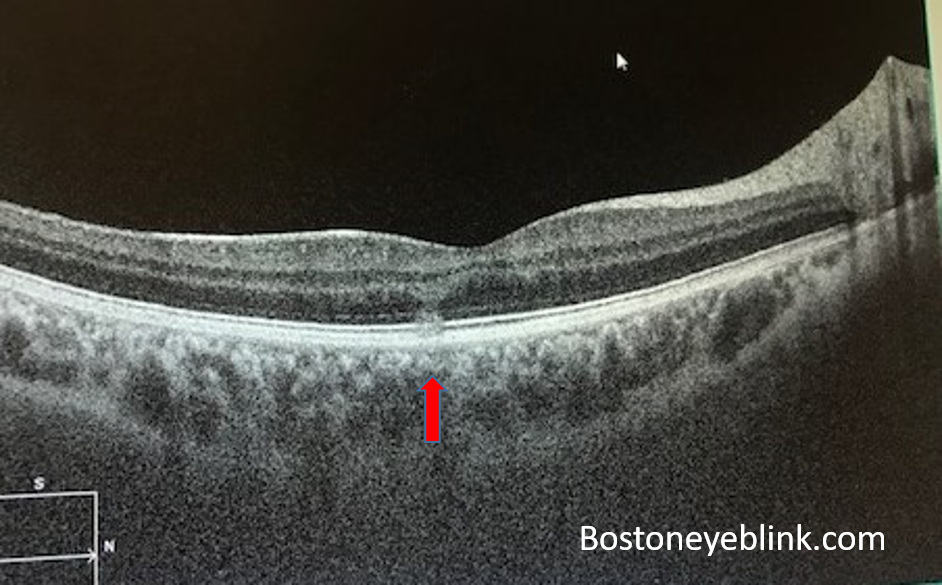

Figure 2 below shows the cross section showing how thick this freckle is.

In my patient’s case, you can see that it is not even a large or thick nevus. However, it is right in the fovea and there is a thin layer of fluid between RPE and the retina, and the foveal region looks significantly thinned out (Figure 2).